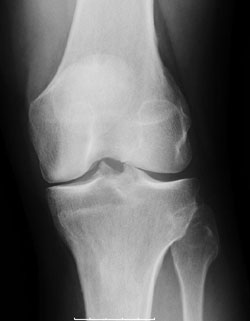

Figure: Medial compartment osteoarthritis

The knee is made up of three compartments: the medial compartment (located on the inside of the knee), the lateral compartment (located on the outside of the knee), and the patellofemoral compartment (located in the front of the knee). In a particular group of osteoarthritis patients, however, the entire knee is not affected by the arthritis. In some patients, only the medial compartment (or, less commonly, only the lateral compartment) may be affected by the disease. For those patients, unicondylar (partial) knee replacement can be considered a treatment option. The term “unicondylar” refers to the replacement of only one section of the smooth bone ends (condyles) – the medial or lateral compartment – as compared to total knee replacement, which involves replacement of all three compartments.